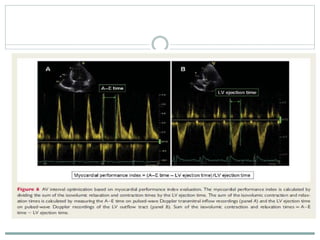

Myocardial performance index (MPI)

 The myocardial performance index is a comprehensive measurement of

LV function. This index is calculated as the sum of isovolumic contraction

and relaxation times divided by the ejection time .

 The optimal AV interval is defined by the lowest myocardial performance

index.